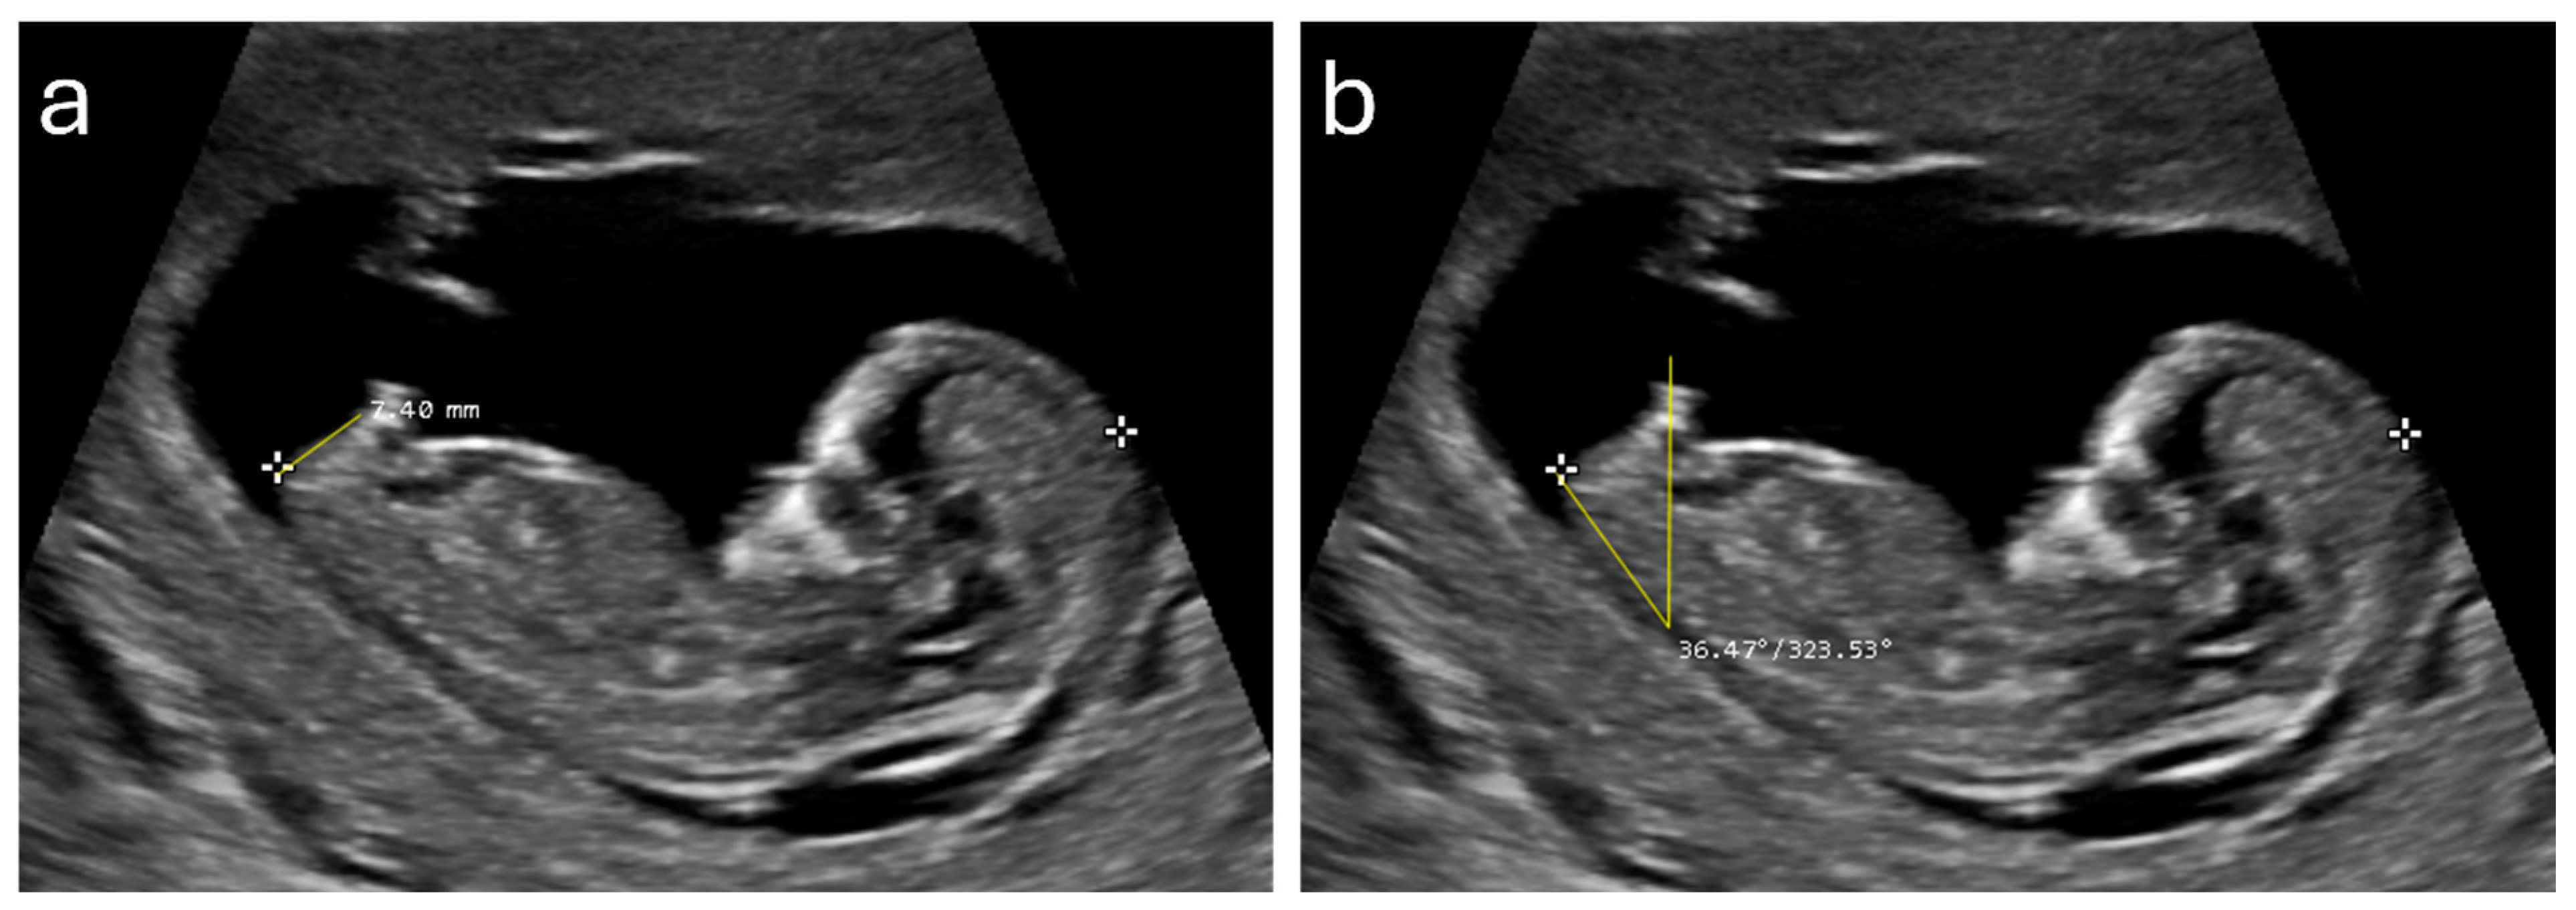

2.3. Ultrasound Measurements